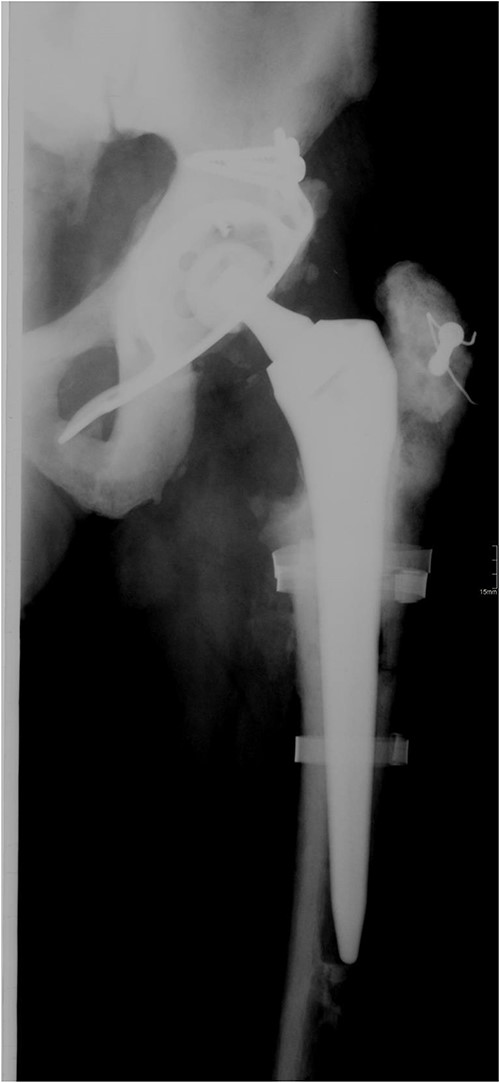

In 2008, the patient complained about increasing pain in the left hip. Laboratory tests were normal and X-ray imaging showed a loose cup which was replaced with a reinforcement ring and a cemented cup and the loose femoral component which was exchanged with a cementless revision stem (Fig. 2). Routine intraoperative tissue samples were positive and Staphylococcus epidermidis was isolated. A 3-month antibiotic treatment consisted of ciprofloxacin and rifampicin successfully cured the infection.

Anteroposterior radiograph of the left hip after revision surgery in 2008.